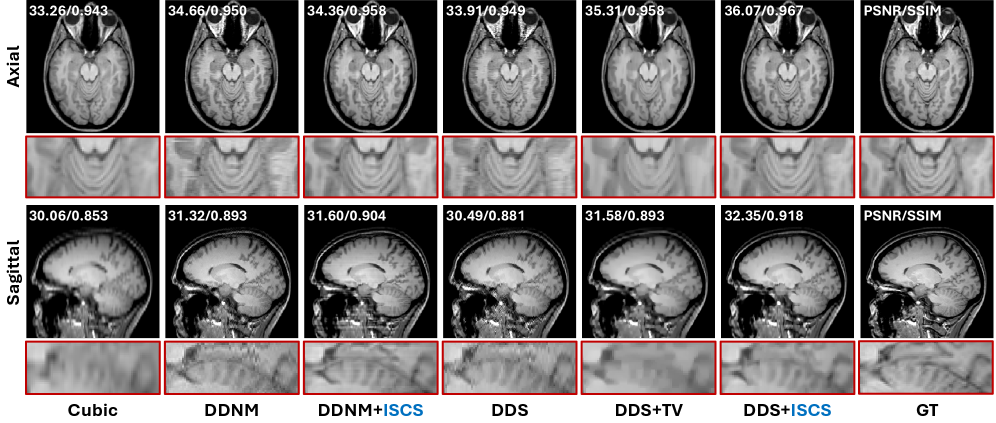

Figure 3: Qualitative results of compared methods on a representative sample for MRI SR of 5×\times.

MRI Isotropic SR

Quantitative comparisons and qualitative visualizations are presented in Table 1 and Fig. 3, respectively. The compared methods exhibit trends consistent with those observed in the CT task when evaluated with and without the proposed ISCS strategy. It is worth noting that the pretrained DM we adopt was trained on coronal slices, so inter-slice inconsistencies mainly manifest in the axial and sagittal views. The results show that ISCS substantially alleviates these inconsistencies without introducing blurring artifacts. In particular, the zoomed sagittal view of the cerebellum in Fig. 3 highlights that, without any inter-slice constraint, both DDNM and DDS produce noticeable streak-like artifacts, whereas TV-based regularization suppresses these artifacts at the cost of oversmoothing structural details. By contrast, incorporating the proposed ISCS yields reconstructions that best preserve fine anatomical structures and are most consistent with the GT.